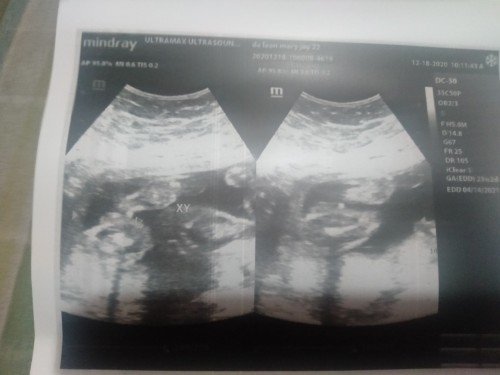

CAS GENDER

sobrang legit yung saya nung nakita ko yung galaw ni baby habang inuultra ako. Ibang iba talaga yung pagmamahal ng ina. π . Boy daw po lumabas. Tama po ba? βΊοΈβΊοΈβΊοΈππππ #pregnancy #1stimemom #theasianparentph #theasianparentph #firstbaby

Soon to be a Mom